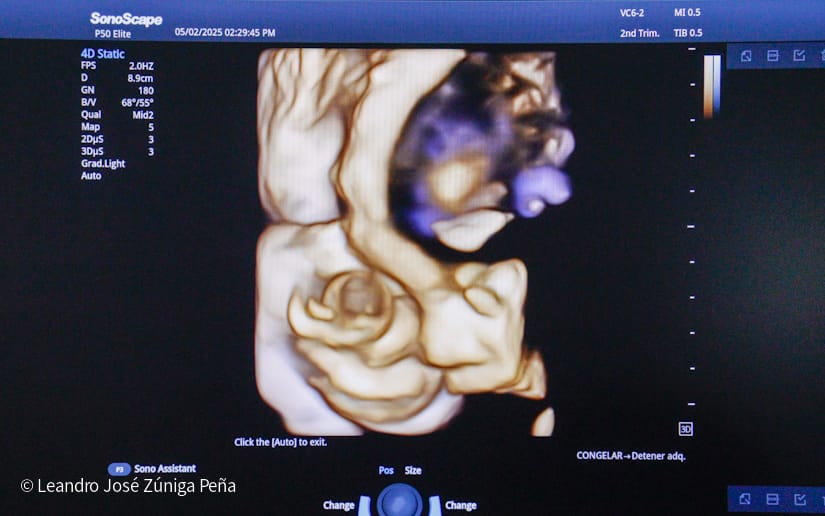

“Con estos ultrasonidos, que son de alta tecnología en el país, estamos completando 32 equipos de ultrasonido que están ubicados en las diferentes unidades de salud. Estos últimos 6 equipos nos van a permitir hacer diagnóstico de manera preventiva a la mujer embarazada, tenemos recursos humanos calificados, médicos especialistas formados por nuestro gobierno, en nuestro país, que tienen todos los conocimientos necesarios para poder hacer diagnóstico de anomalías congénitas, diagnóstico prenatal de alteraciones en la embarazada y en el feto y poder hacer prevención de la preclancia, el parto prematuro, la restricción del crecimiento fetal o bajo peso, que son morbilidades que afectan a nuestras embarazadas y a nuestro recién nacido, de igual manera, la tecnología volumétrica que se ha adquirido en estos equipos como el 3D y el 4D permite obtener mejores imágenes de anomalías congénitas para que estas pacientes que son captadas en estas unidades puedan ser referidas al Bertha Calderón”, explicó el especialista.